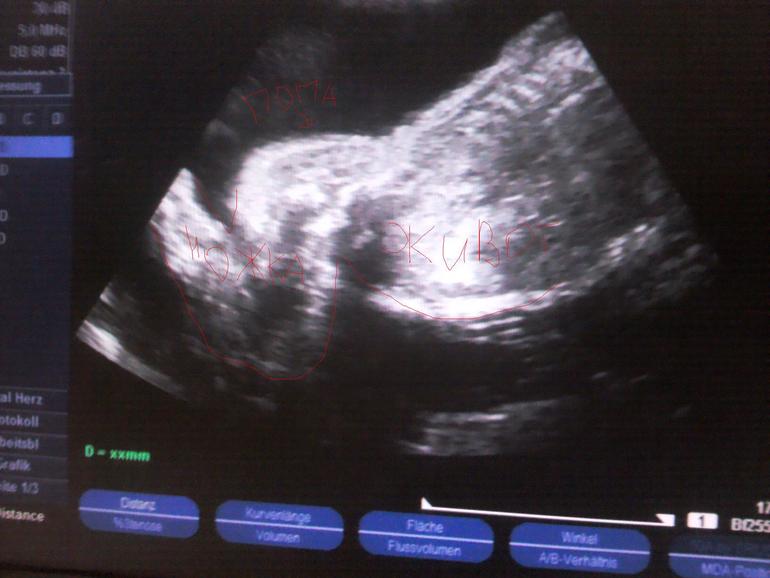

Еще вчера мы были на Узи,слава богу у нас все хорошо.

Показали мне сердечка,каждый из 4 отсеков прослушали,показали мозг,позвоночник,лопатки,плечики,коленки,ребрышки,пальчики на ручках и ножках)В общем отклонений не выявлено,могу спать спокойно)У нас так и осталось обвитие пуповинкой,но сказали,что оно легкое,как шарфик.Положение плода поперечное,ножками как раз мне в ребра бьет)

Все у нас соответствует сроку,кроме ножек,они у нас длинные для нашего срока,в папу пошел малышок)

И еще мое чудо упорно,не хочет показывать кто же он все таки,мальчик или девочка)

Ножки сдвигает,пуповинка между ножек,в общем Киндер-сюрприз)

УЗИ